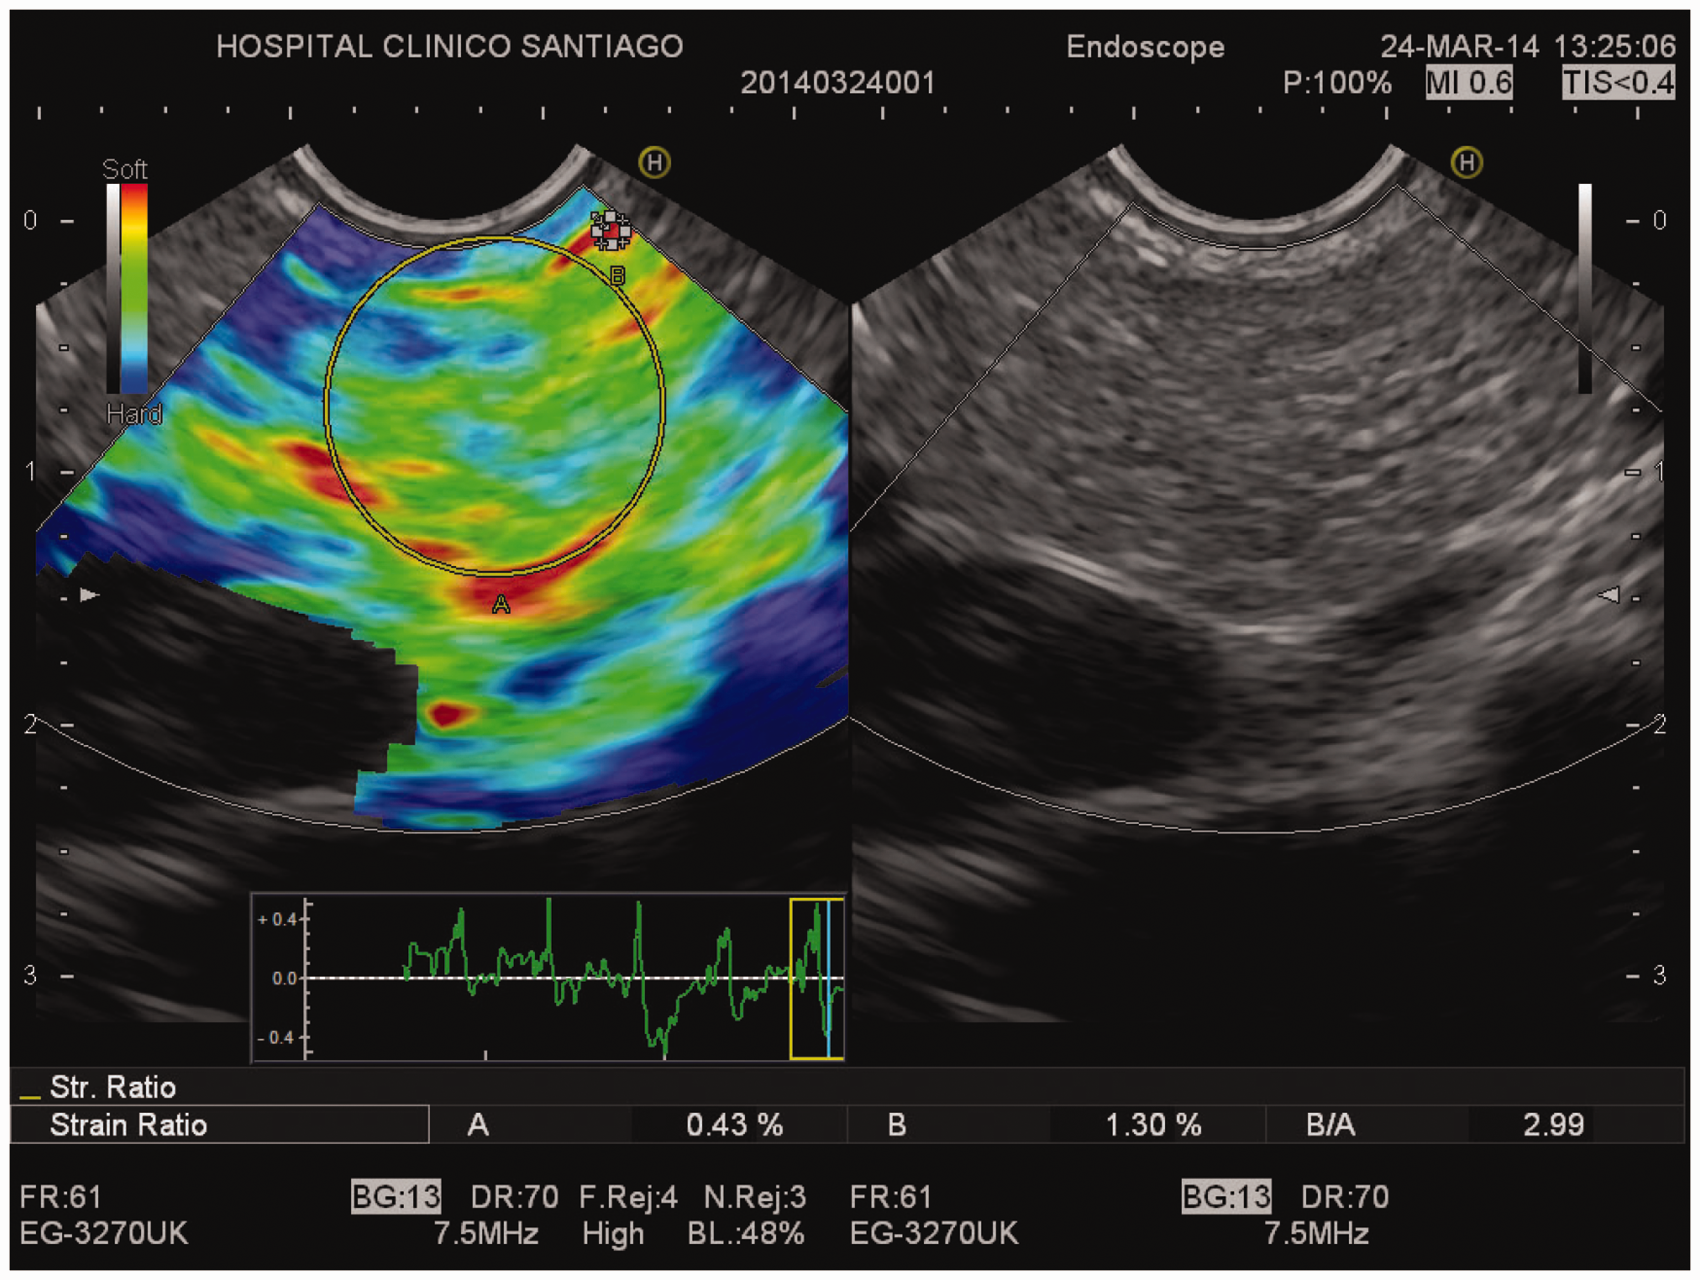

Endoscopic ultrasound (EUS) and EUS-guided elastographic evaluation of the pancreas. Right picture: B-mode EUS showing mild pancreatic abnormalities (hyperechoic foci, strands, hyperechoic pancreatic duct wall with duct irregularity). Left picture: EUS-guided elastography showing pancreatic fibrosis (strain ratio 2.99).

Two different areas (A and B) were selected: area A was the largest possible area of the pancreatic parenchyma. Area B referred to a soft (red) reference area, corresponding to normal surrounding gut wall. The result of the elastographic evaluation was defined as the quotient B/A (strain ratio, SR). The mean SR at the head, body and tail of the pancreas was considered as the result of the elastographic evaluation (normal SR <2.25).

All 53 patients had an abnormally high SR at EUS-elastography (3.94 ± 1.57) (Figures 3 and 4). Bicarbonate concentration peak in duodenal fluid during the ePFT was 64.7 ± 23.9 mEq/l (Figure 4). An abnormally low bicarbonate peak was observed in 43 patients (81.1%). Finally, compliance of the pancreatic duct was reduced in 41 patients (77.3%) (Figure 4). Basal diameter of the main pancreatic duct at the pancreas body in these patients before intravenous secretin injection was 1.7 ± 0.4 mm, whereas maximal diameter after intravenous secretin was 2.2 ± 0.5 mm.